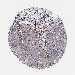

Basal cell and squamous cell cancer

SKIN CANCER - Protein expressioni

A mouse-over function shows sample information and annotation data. Click on an image to view it in a full screen mode. Samples can be filtered based on level of antibody staining by selecting one or several of the following categories: high, medium, low and not detected. The assay and annotation is described here.

Each image is clickable and will lead to virtual microscopy that enables deeper exploration of all samples and also displays staining intensity scores, fraction scores and subcellular localization as well as patient and tissue information for each sample.

Antibody HPA041766

Antibody HPA048639

Basal cell carcinoma

Squamous cell carcinoma, NOS

Squamous cell carcinoma, metastatic, NOS

Squamous cell carcinoma in situ, NOS